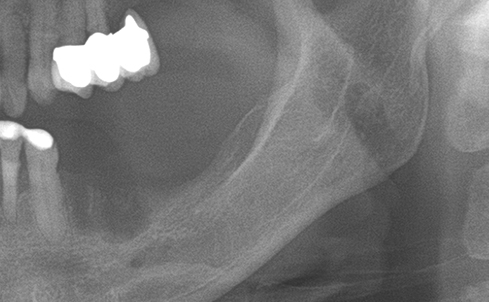

Simultaenous bone grafting for implants

Partial edentulous clinical cases

Implants/Bone Grafting